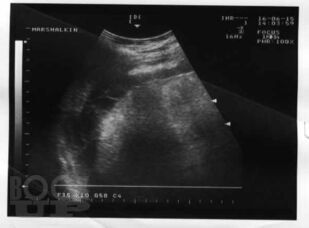

Материалом послужили данные многолетнего обследования больных декомпенсированным циррозом печени, проанализированы клинические проявления спонтанного бактериального перитонита, в том числе системной воспалительной реакции, использован широкий комплекс современных методов: подсчет полиморфноядерных нейтрофилов в асцитической жидкости, микробиологическое исследование крови и асцита, ультразвуковая оценка акустической однородности асцита, исследовано содержание цитокинов, С-реактивного белка, количественный и качественный состав химических компонентов – маркеров потенциальных возбудителей инфекции асцитической жидкости методом газовой хроматографии-масс-спектрометрии. В работе представлены результаты исследования позволяющие диагностировать спонтанный бактериальный перитонит на более ранних сроках, что позволяет проводить своевременную адекватную терапию. Рассмотрены вопросы дифференциальной диагностики первичного и вторичного бактериального перитонита, приведены яркие клинические примеры, отражающие трудности диагностики.

В книге на основе анализа литературы и собственных данных автором представлены современные аспекты этиологии, патогенеза, диагностики, профилактики и лечения спонтанного бактериального перитонита у больных циррозом печени. Материалом послужили данные многолетнего обследования больных декомпенсированным циррозом печени, проанализированы клинические проявления спонтанного бактериального перитонита, в том числе системной воспалительной реакции, использован широкий комплекс современных методов: подсчет полиморфноядерных нейтрофилов в асцитической жидкости, микробиологическое исследование крови и асцита, ультразвуковая оценка акустической однородности асцита, исследовано содержание цитокинов, С-реактивного белка, количественный и качественный состав химических компонентов – маркеров потенциальных возбудителей инфекции асцитической жидкости методом газовой хроматографии-масс-спектрометрии.